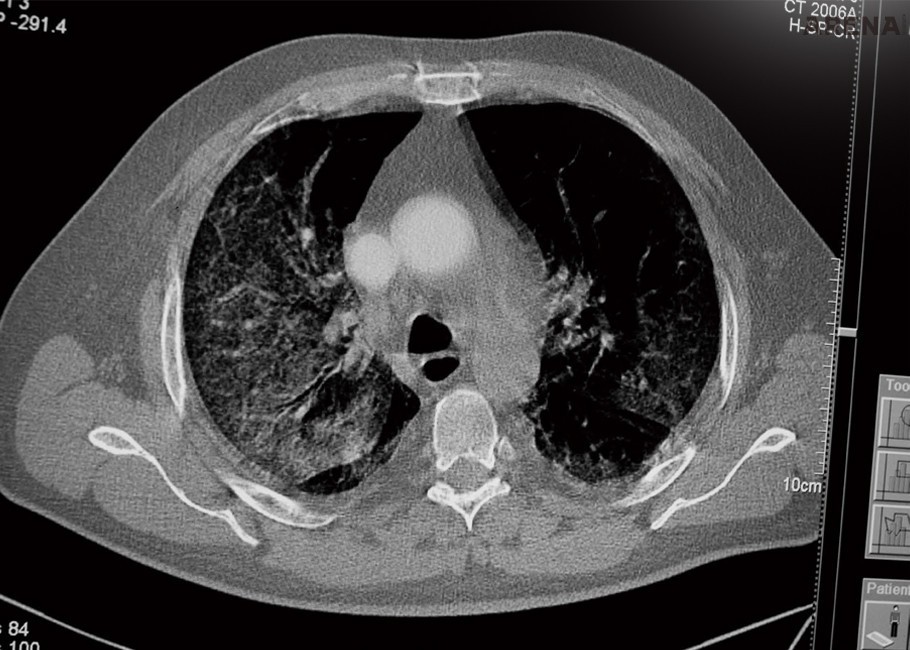

ITALY Catania, Sicilia. April 9 2020.

CT scan of the lungs of a patient with Covid 19 virus.

위 사진은 2020년 4월 9일, 코로나19에 감염된 사람의 폐를 CT 촬영한 것이다.

바이러스가 폐 혈관을 따라 걷잡을 수 없이 퍼진 적나라한 이미지는 바이러스에 대한 공포와 경각심을 불러일으킨다.